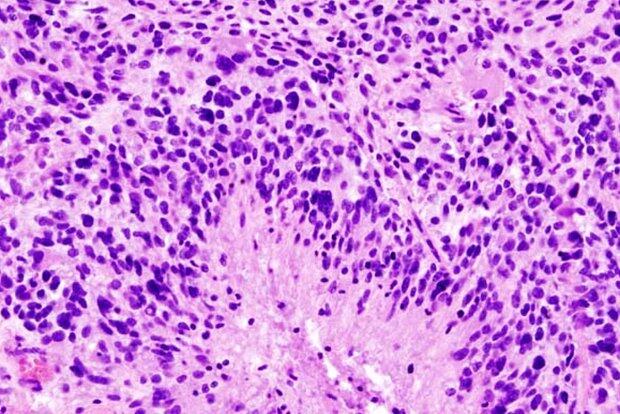

Ученые из Медицинского колледжа Альберта Эйнштейна показали, что глиобластома - самый агрессивный вид рака мозга - поражает не только мозг, но и кости черепа. Исследование, опубликованное в Nature Neuroscience (NN), выявило: опухоль разрушает черепные швы, изменяет состав костного мозга и нарушает работу иммунной системы, передает Day.Az со ссылкой на Lenta.ru.

Эксперименты на мышах и анализ снимков пациентов показали, что глиобластома вызывает истончение костей и расширение каналов между черепом и мозгом. По этим каналам к опухоли устремляются воспалительные клетки из костного мозга, делая ее более агрессивной и устойчивой к лечению.

Ученые зафиксировали серьезный дисбаланс иммунных клеток: увеличивается число воспалительных нейтрофилов, а защитные B-клетки почти исчезают. Это может объяснять, почему традиционные методы терапии, ориентированные только на мозг, оказываются малоэффективны.